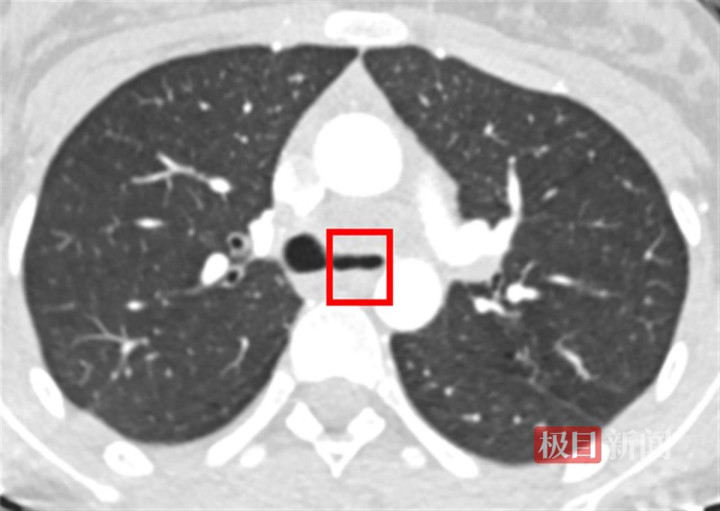

左主支气管被挤压成一条缝隙(CT影像以镜像方式呈现,左右与实际颠倒)

9月30日,小姜被紧急转入湖北省内唯一的三甲呼吸疾病专科医院——武汉市肺科医院。经过一系列检查,医生们发现结核杆菌不仅侵犯了她的肺部,还形成了结核性脓胸,即胸腔壁被病菌侵蚀、化脓,继而形成纤维板。更为严重的是,左主气管周围的纵隔也被结核菌侵犯,形成了脓包病灶,紧紧挤压着左主气管。在CT上,医生可以清晰地看到左主支气管已被压成了一条细缝。同时,耐药检测也显示,小姜感染的是更为难缠的耐药结核菌,常规抗结核药对它束手无策。